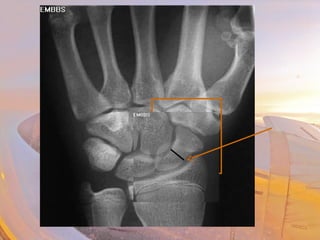

CCaarrppaallss

• Scaphoid

–Anatomical snuff box

–Most often broken with fall (FOOSH)

–Needs to be cast even if no evidence of a fx

• Fx will show up 10 days later